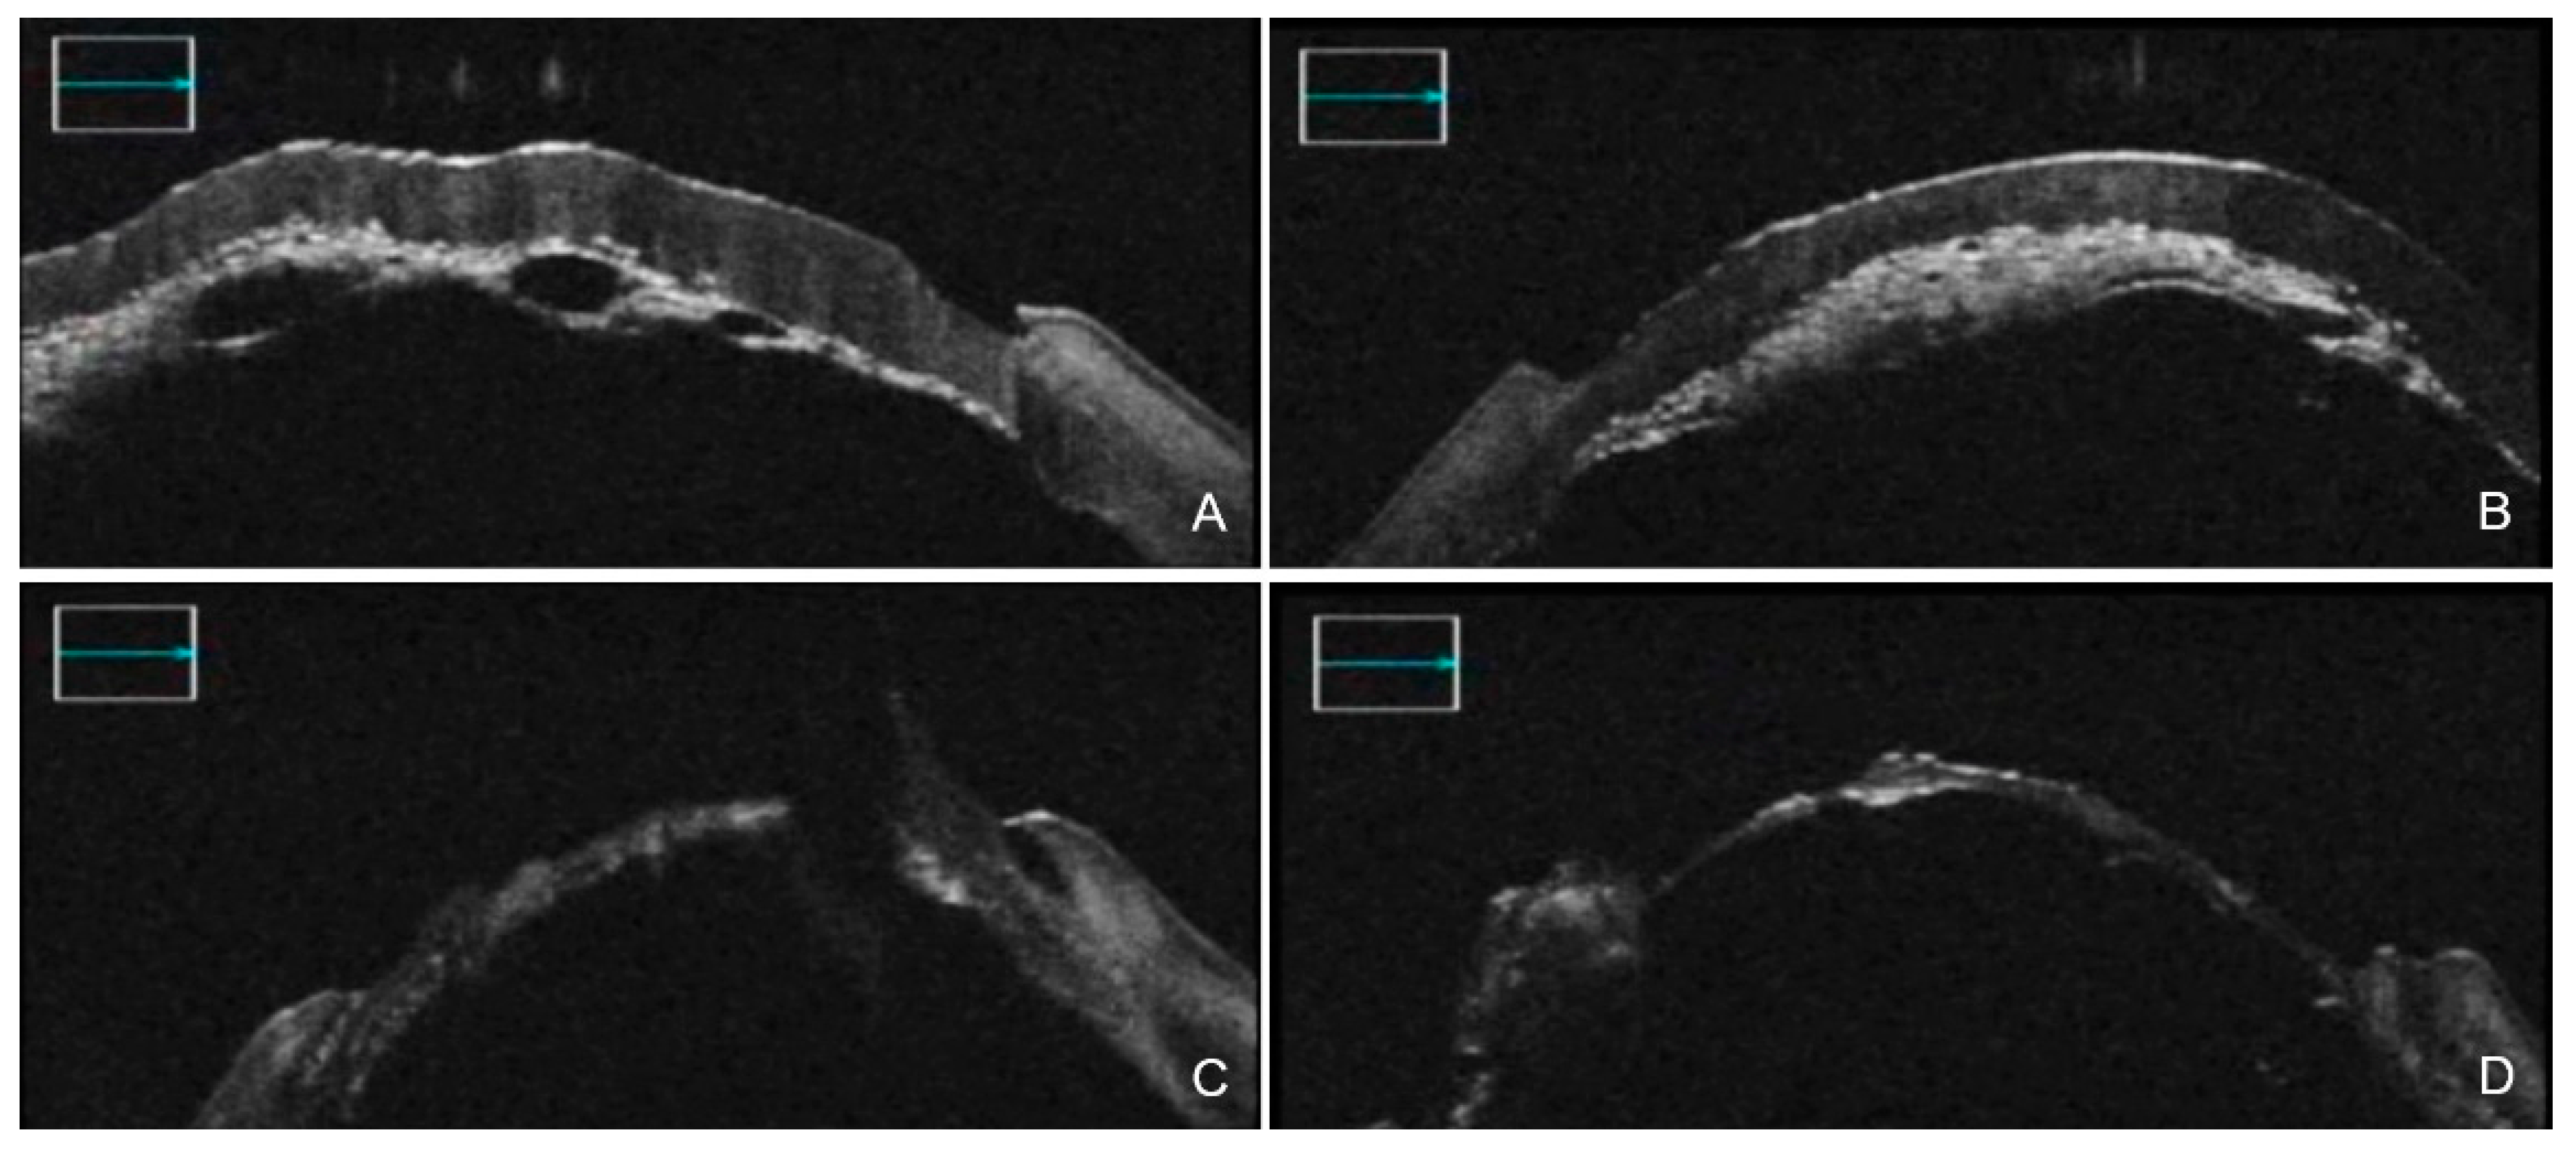

3. iOCT-Assisted DALK

4. iOCT-Assisted Endothelial Keratoplasty

4.1. iOCT-Aided DSAEK

4.2. iOCT-Aided DMEK